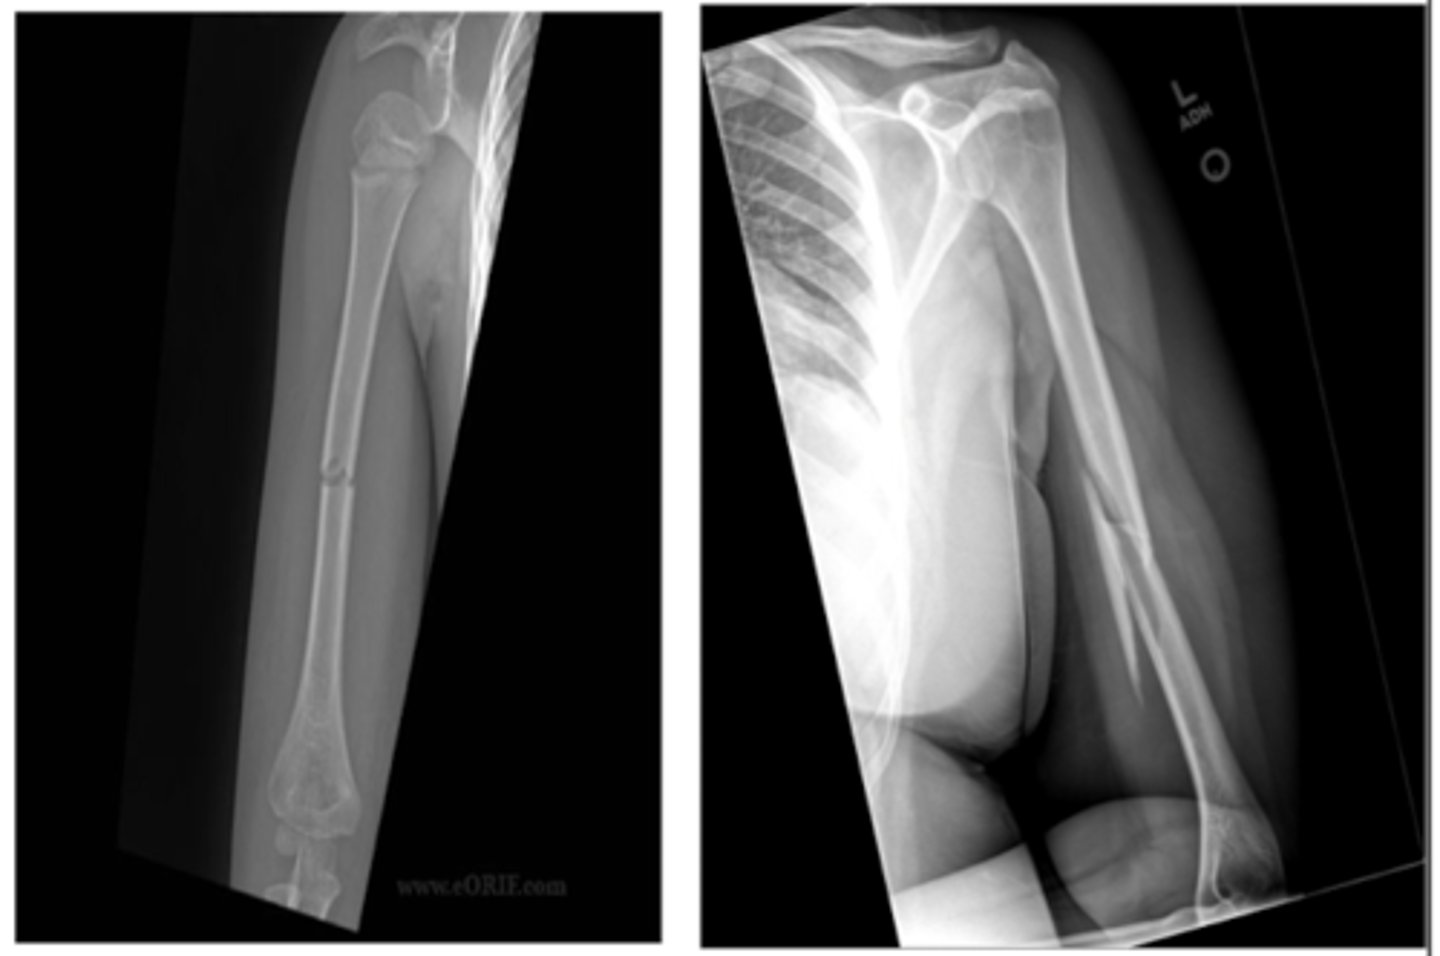

What nerve is most commonly injured with a humeral shaft fracture? What S/S suggest injury?

radial

- will be unable to extend wrist/fingers

- lose sensation on the dorsum of the hand

Wrist drop is most often seen in what type of nerve injury?

radial (Saturday night/Crutch palsy)

T/F. Most humeral shaft fractures are treated non-surgically.

TRUE

If needed, what are THREE surgical options for a humeral shaft fracture?

IM rod

ORIF

External fixation

What is a common complication of a humeral shaft fracture?

malunion